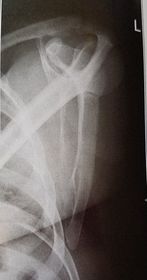

| Inferosuperior Axiolateral Shoulder | humerus is foreshortened - humeral head is distorted arm is not abducted 90 degrees from body |